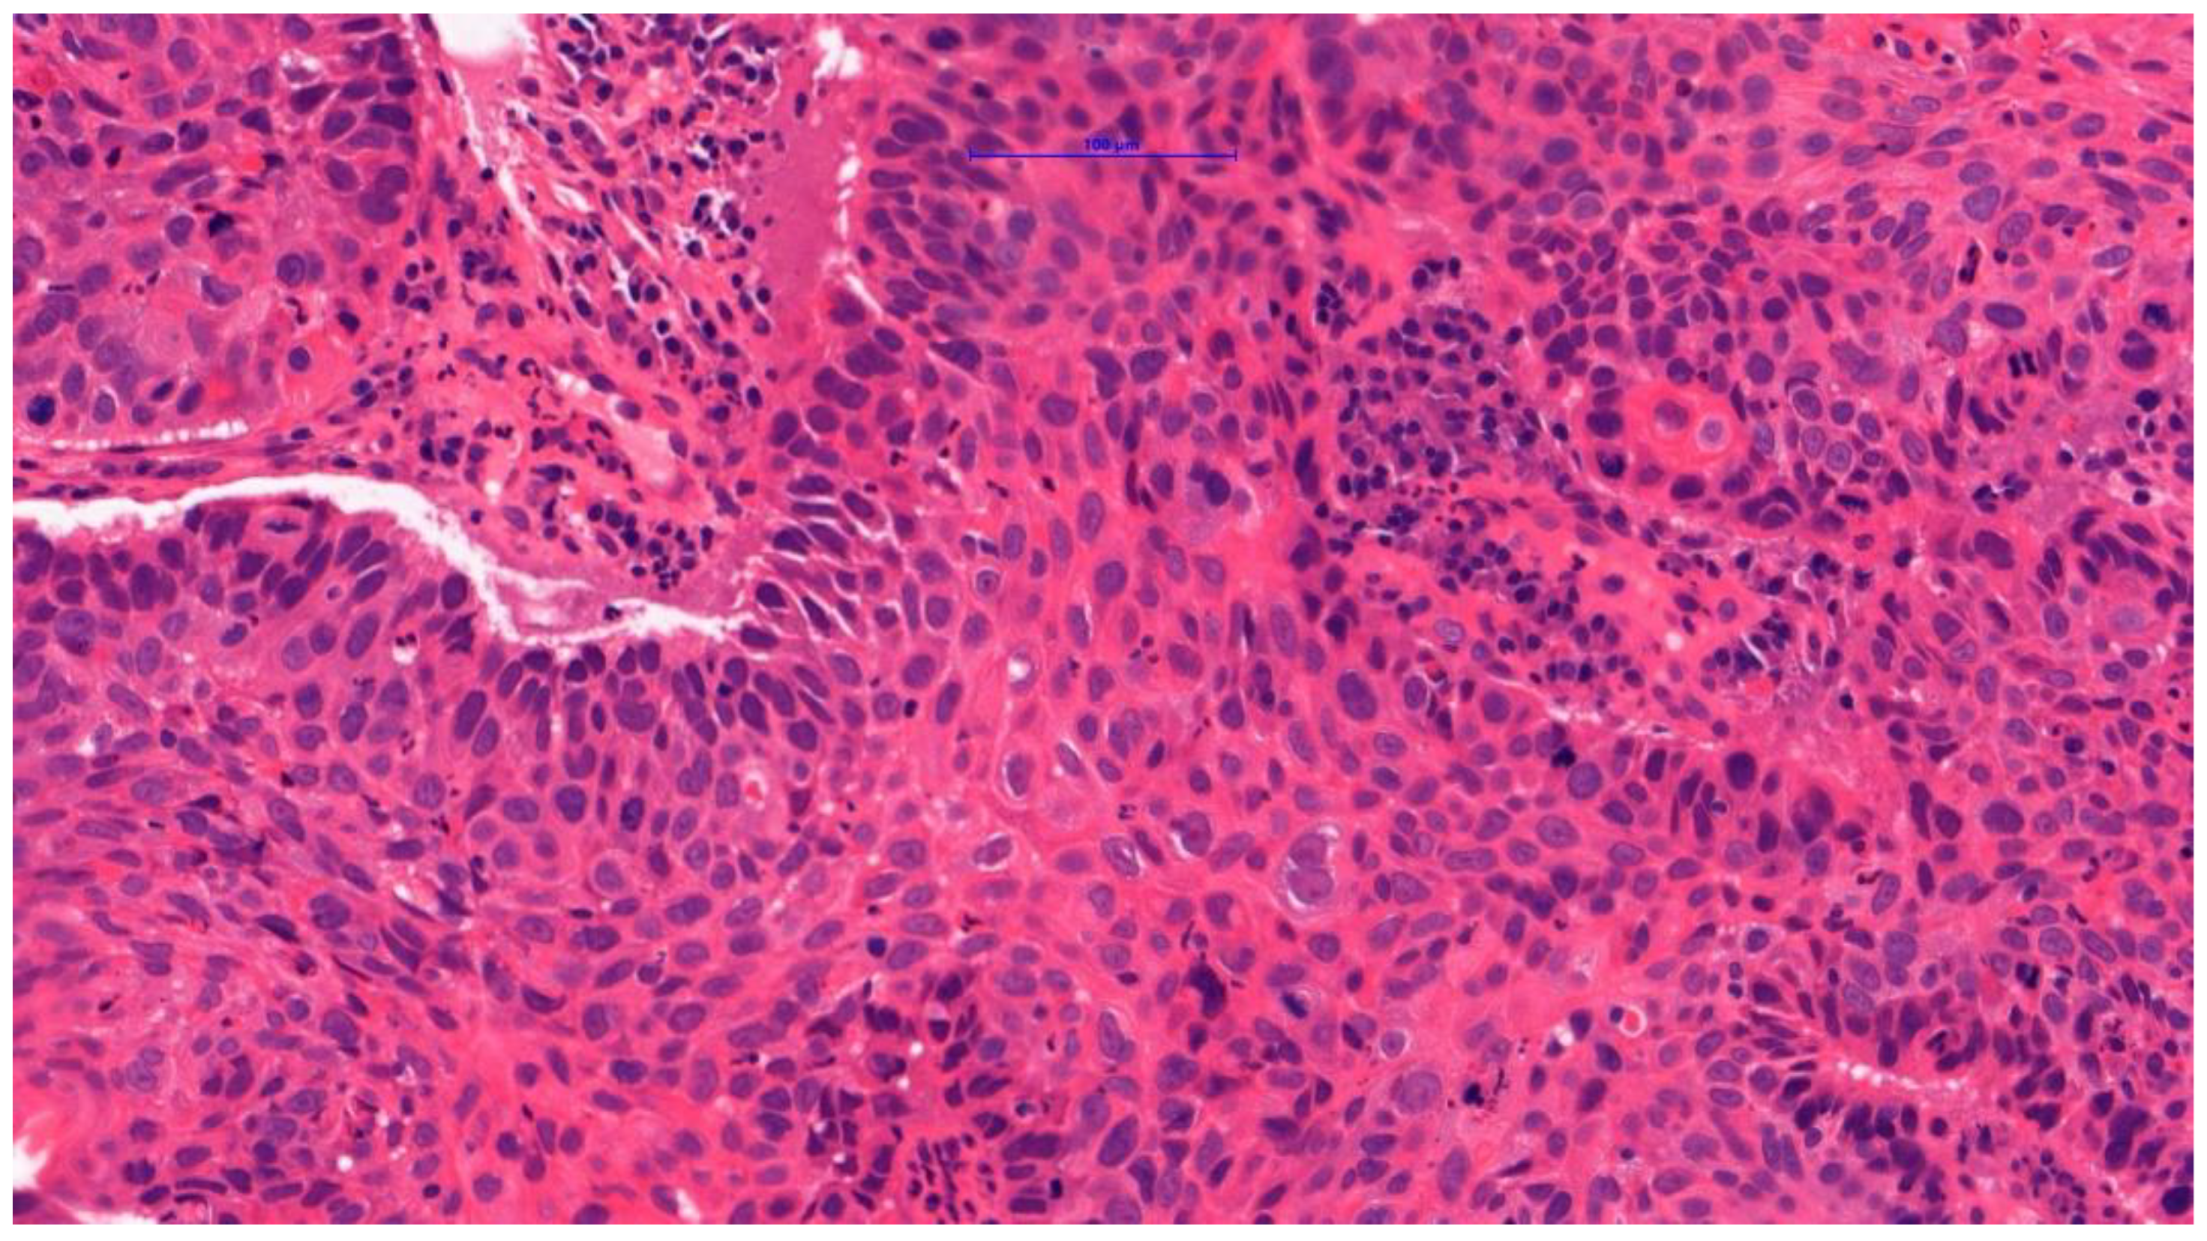

4.1. LSCC Group

| G1-2, n (%) | 166 (83.0) |

| G3, n (%) | 34 (17.0) |